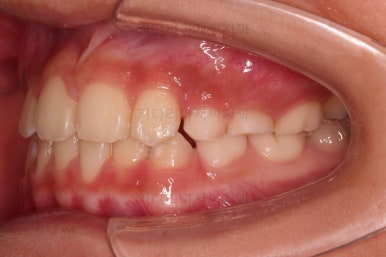

CASE 1.

나이 : 9세

총 치료기간 : 3개월

바로 전후 비교사진 올립니다.

골격의 문제가 없었고 골격에 대한 치료가 아니었지만 얼굴 모습도 약간의변화가 있죠?

함몰감이 약간 있던 윗입술 부분이 볼륨감이 생기면서 자연스러운 아이얼굴 비율이 되었어요.

치열도 자연스럽게 예뻐졌네요.

3개월만에요😄

이 후에 프리올소라는 장치로 유지과정 중입니다.

치료를 프리올소로 한건 아니지만 장기적으로 재발의 요인이 몇 가지 관찰되어 유지장치 겸 해서 사용 중이죠.